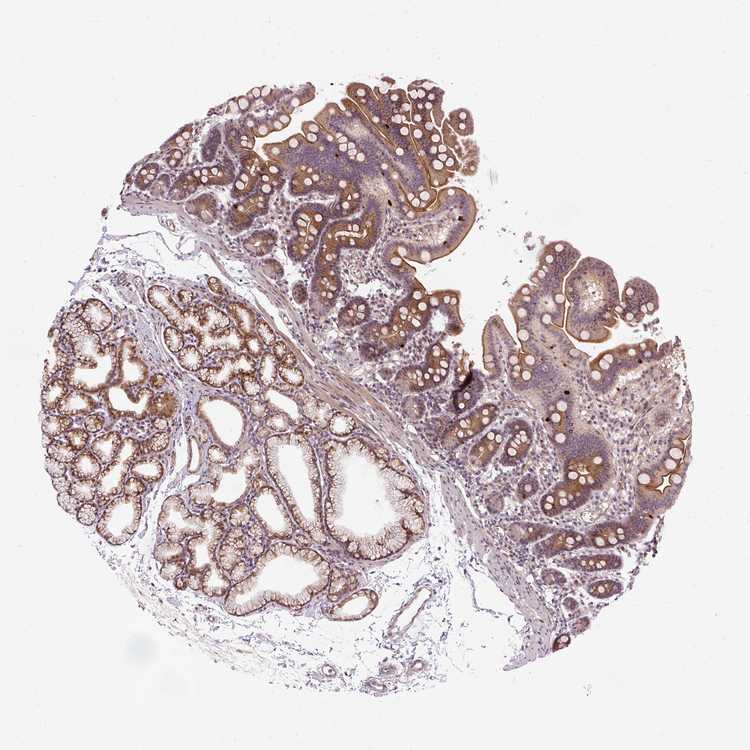

TISSUE PRIMARY DATA DUODENUM Show tissue menu

DUODENUM - Expression summary

DUODENUM - Antibody stainingi

Antibody staining in the annotated cell types in the current human tissue is reported as not detected, low, medium, or high, based on conventional immunohistochemistry profiling in selected tissues. This score is based on the combination of the staining intensity and fraction of stained cells. Each image is clickable and will lead to virtual microscopy that enables deeper exploration of all samples and also displays staining intensity scores, fraction scores and subcellular localization as well as patient and tissue information for each sample.

Antibody HPA034489Antibody HPA034490

Glandular cells HighMedium